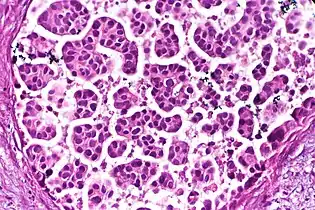

This can be done to slides processed by the chemical fixation or frozen section slides. To see the tissue under a microscope, the sections are stained with one or more pigments. The aim of staining is to reveal cellular components; counterstains are used to provide contrast.

The most commonly used stain in histology is a combination of hematoxylin and eosin (often abbreviated H&E). Hematoxylin is used to stain nuclei blue, while eosin stains the cytoplasm and the extracellular connective tissue matrix of most cells pink. There are hundreds of various other techniques which have been used to selectively stain cells. Other compounds used to color tissue sections include safranin, Oil Red O, congo red, silver salts and artificial dyes. Histochemistry refers to the science of using chemical reactions between laboratory chemicals and components within tissue. A commonly performed histochemical technique is the Perls' Prussian blue reaction, used to demonstrate iron deposits in diseases like Hemochromatosis.[2]

Recently, antibodies have been used to stain particular proteins, lipids and carbohydrates. Called immunohistochemistry, this technique has greatly increased the ability to specifically identify categories of cells under a microscope. Other advanced techniques include in situ hybridization to identify specific DNA or RNA molecules. These antibody staining methods often require the use of frozen section histology. These procedures above are also carried out in the laboratory under scrutiny and precision by a trained specialist medical laboratory scientist (a histoscientist). Digital cameras are increasingly used to capture histopathological images.